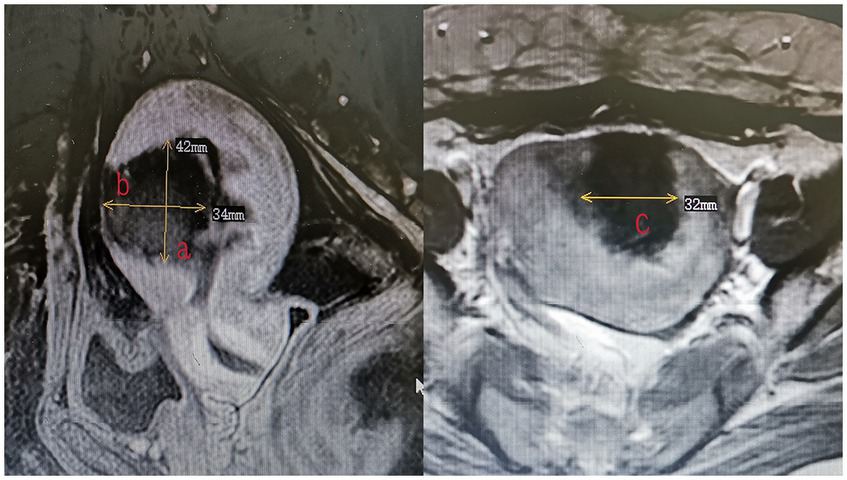

All patients underwent MRI within 3 days after HIFU to define the condition of the endometrium and evaluate the non-perfused volume (NPV). The volume of adenomyotic lesions and NPV were measured using the following equation for the prolate ellipsoid (7): volume = 0.5233 × a × b × c (a, b, and c are the longitudinal, anteroposterior, and transverse dimensions, respectively). The volume of adenomyotic lesions was defined as the volume of the part of the uterus where the focal adenomyotic lesions were located (Figure 1). The volume of the ablation lesions was defined as the volume of the non-perfused area (Figure 2). The NPV ratio (NPVR) was defined as the NPV divided by the lesion volume, NPVR = NPV/volume of the adenomyotic lesion × 100%. Successful treatment with HIFU was defined as an NPV of ≥1 cm3 in the planned ablation zone (8).

Figure 1

The measurement of the volume of adenomyotic lesions (volume = 0.5233 × a × b × c).